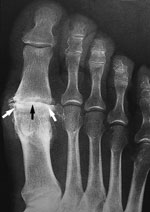

This x-ray reveals osteoarthritis in the metatarsophalangeal joint of the big toe. Joint space narrowing (black arrow) and bone spurs (white arrows) can be seen.

Reproduced from Johnson TR, Steinbach LS (eds): Essentials of Musculoskeletal Imaging. Rosemont, IL American Academy of Orthopaedic Surgeons, 2004, p. 631.

X-rays. These imaging tests provide detailed pictures of dense structures such as bone. An x-ray of an arthritic foot may show narrowing of the joint space between bones (an indication of cartilage loss), changes in the bone (such as fractures), or the formation of bone spurs.

Weight-bearing x-rays are taken while you stand. They are the most valuable additional test in diagnosing the severity of arthritis and noting any joint deformity associated with it. In arthritic conditions, if x-rays are taken without standing, it is difficult to assess how much arthritis is present, where it is located in the joint, and how much deformity is present. So, it is very important that, when possible, x-rays are taken standing.